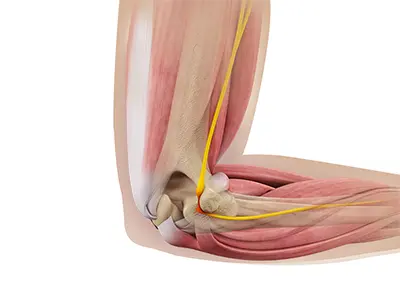

Cubital Tunnel Syndrome (Ulnar Nerve Entrapment)

When the elbow is bent, the ulnar nerve can stretch and catch on the bony bump. When the ulnar nerve is compressed or entrapped, the nerve can tear and become inflamed, leading to cubital tunnel syndrome.